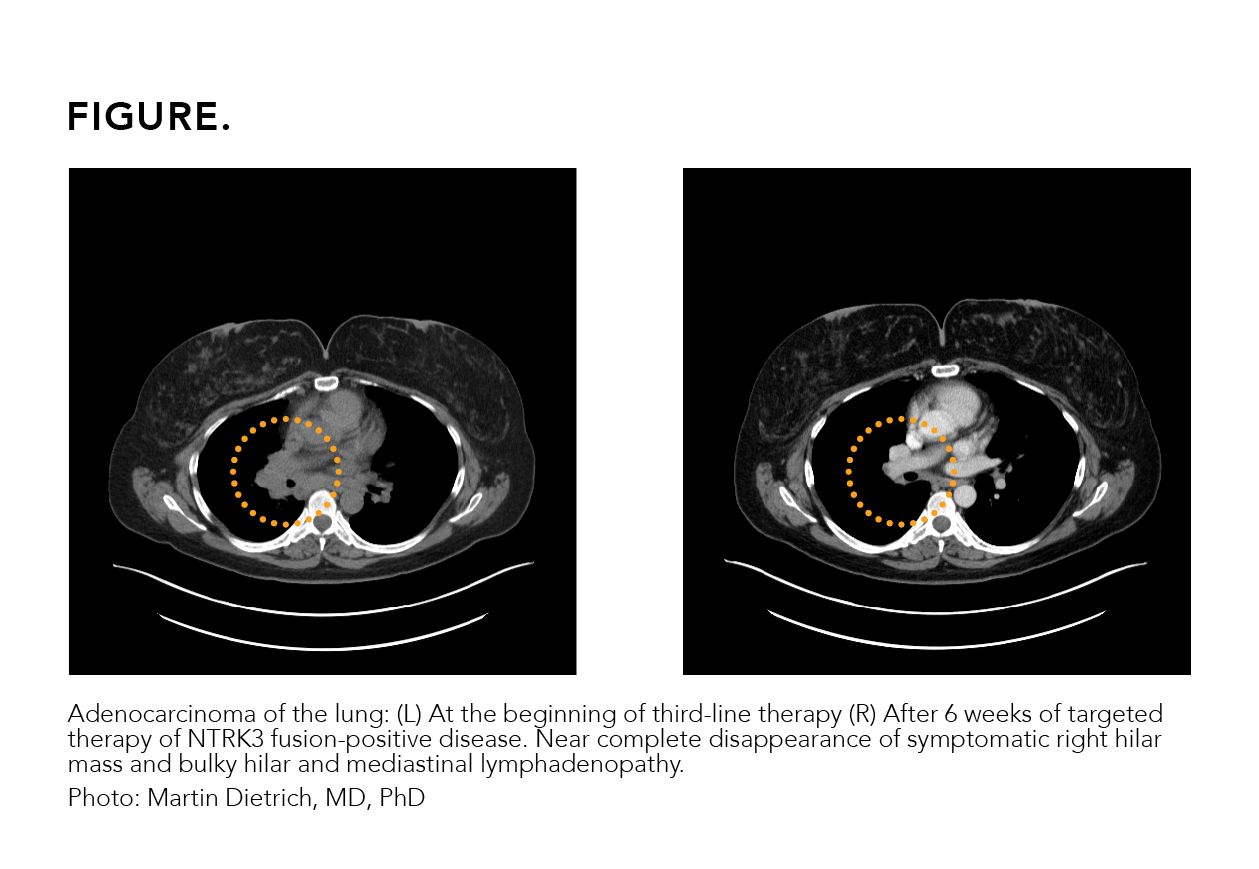

A 41-year-old female patient received a diagnosis of adenocarcinoma of the lung after presenting with shortness of breath. Her biopsy revealed a PD-L1 level of 80% and no actionable mutation was seen on liquid biopsy. No additional tissue was available for genomic testing. The patient was initiated on single-agent immunotherapy and showed disease progression on the first follow-up scans. Chemotherapy was then added to immunotherapy, stabilizing her disease for 3 months prior to clinical progression. A repeat tissue biopsy was obtained and retested on an RNA-based

tissue platform. An NTRK3 fusion was identified, and the patient was started on targeted therapy with near complete response on the first follow-up scan (Figure).

FIGURE.